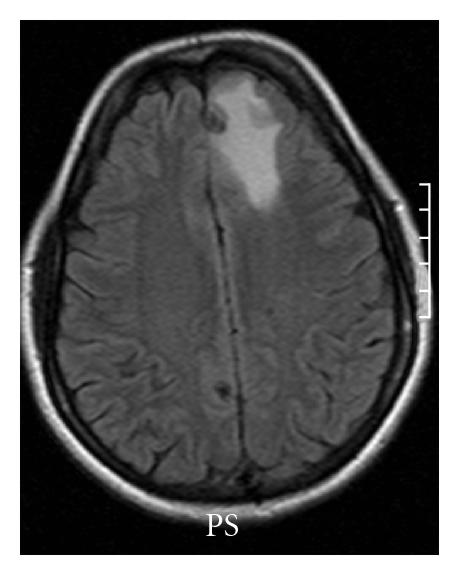

There has been increasing evidence that perilesional edema, which occurs episodically, is associated with seizures [14, 15, 18–20]. Perilesional edema appears as a bright signal using magnetic resonance imaging (MRI) FLAIR or T2 imaging (Figure 1). It is almost always accompanied by enhancement around the calcified focus [11]. Previously calcified NCC has been classified as the inactive form of the disease, suggesting that it is less important than other forms of NCC [21]. Recently a growing literature is finding that perilesional edema related to calcifications seems to be a relatively frequent phenomenon, with reports ranging from 23%–35% in literature [8, 14, 22]. The natural history or pathophysiology of perilesional edema is not yet known, but it appears that it recurs, and repeated episodes tend to be associated with the same lesions in a patient. In a recent prospective nested case-control study, 110 patients with seizures or headaches and calcified lesions in an endemic region were followed for recurrent seizures. Of those with recurrent seizures, perilesional edema was noted on MRI in 50% as opposed to 9% of asymptomatic matched controls [23]. This study suggests that perilesional edema is a common and potentially preventable cause of seizure in endemic regions.

(a)

(b)